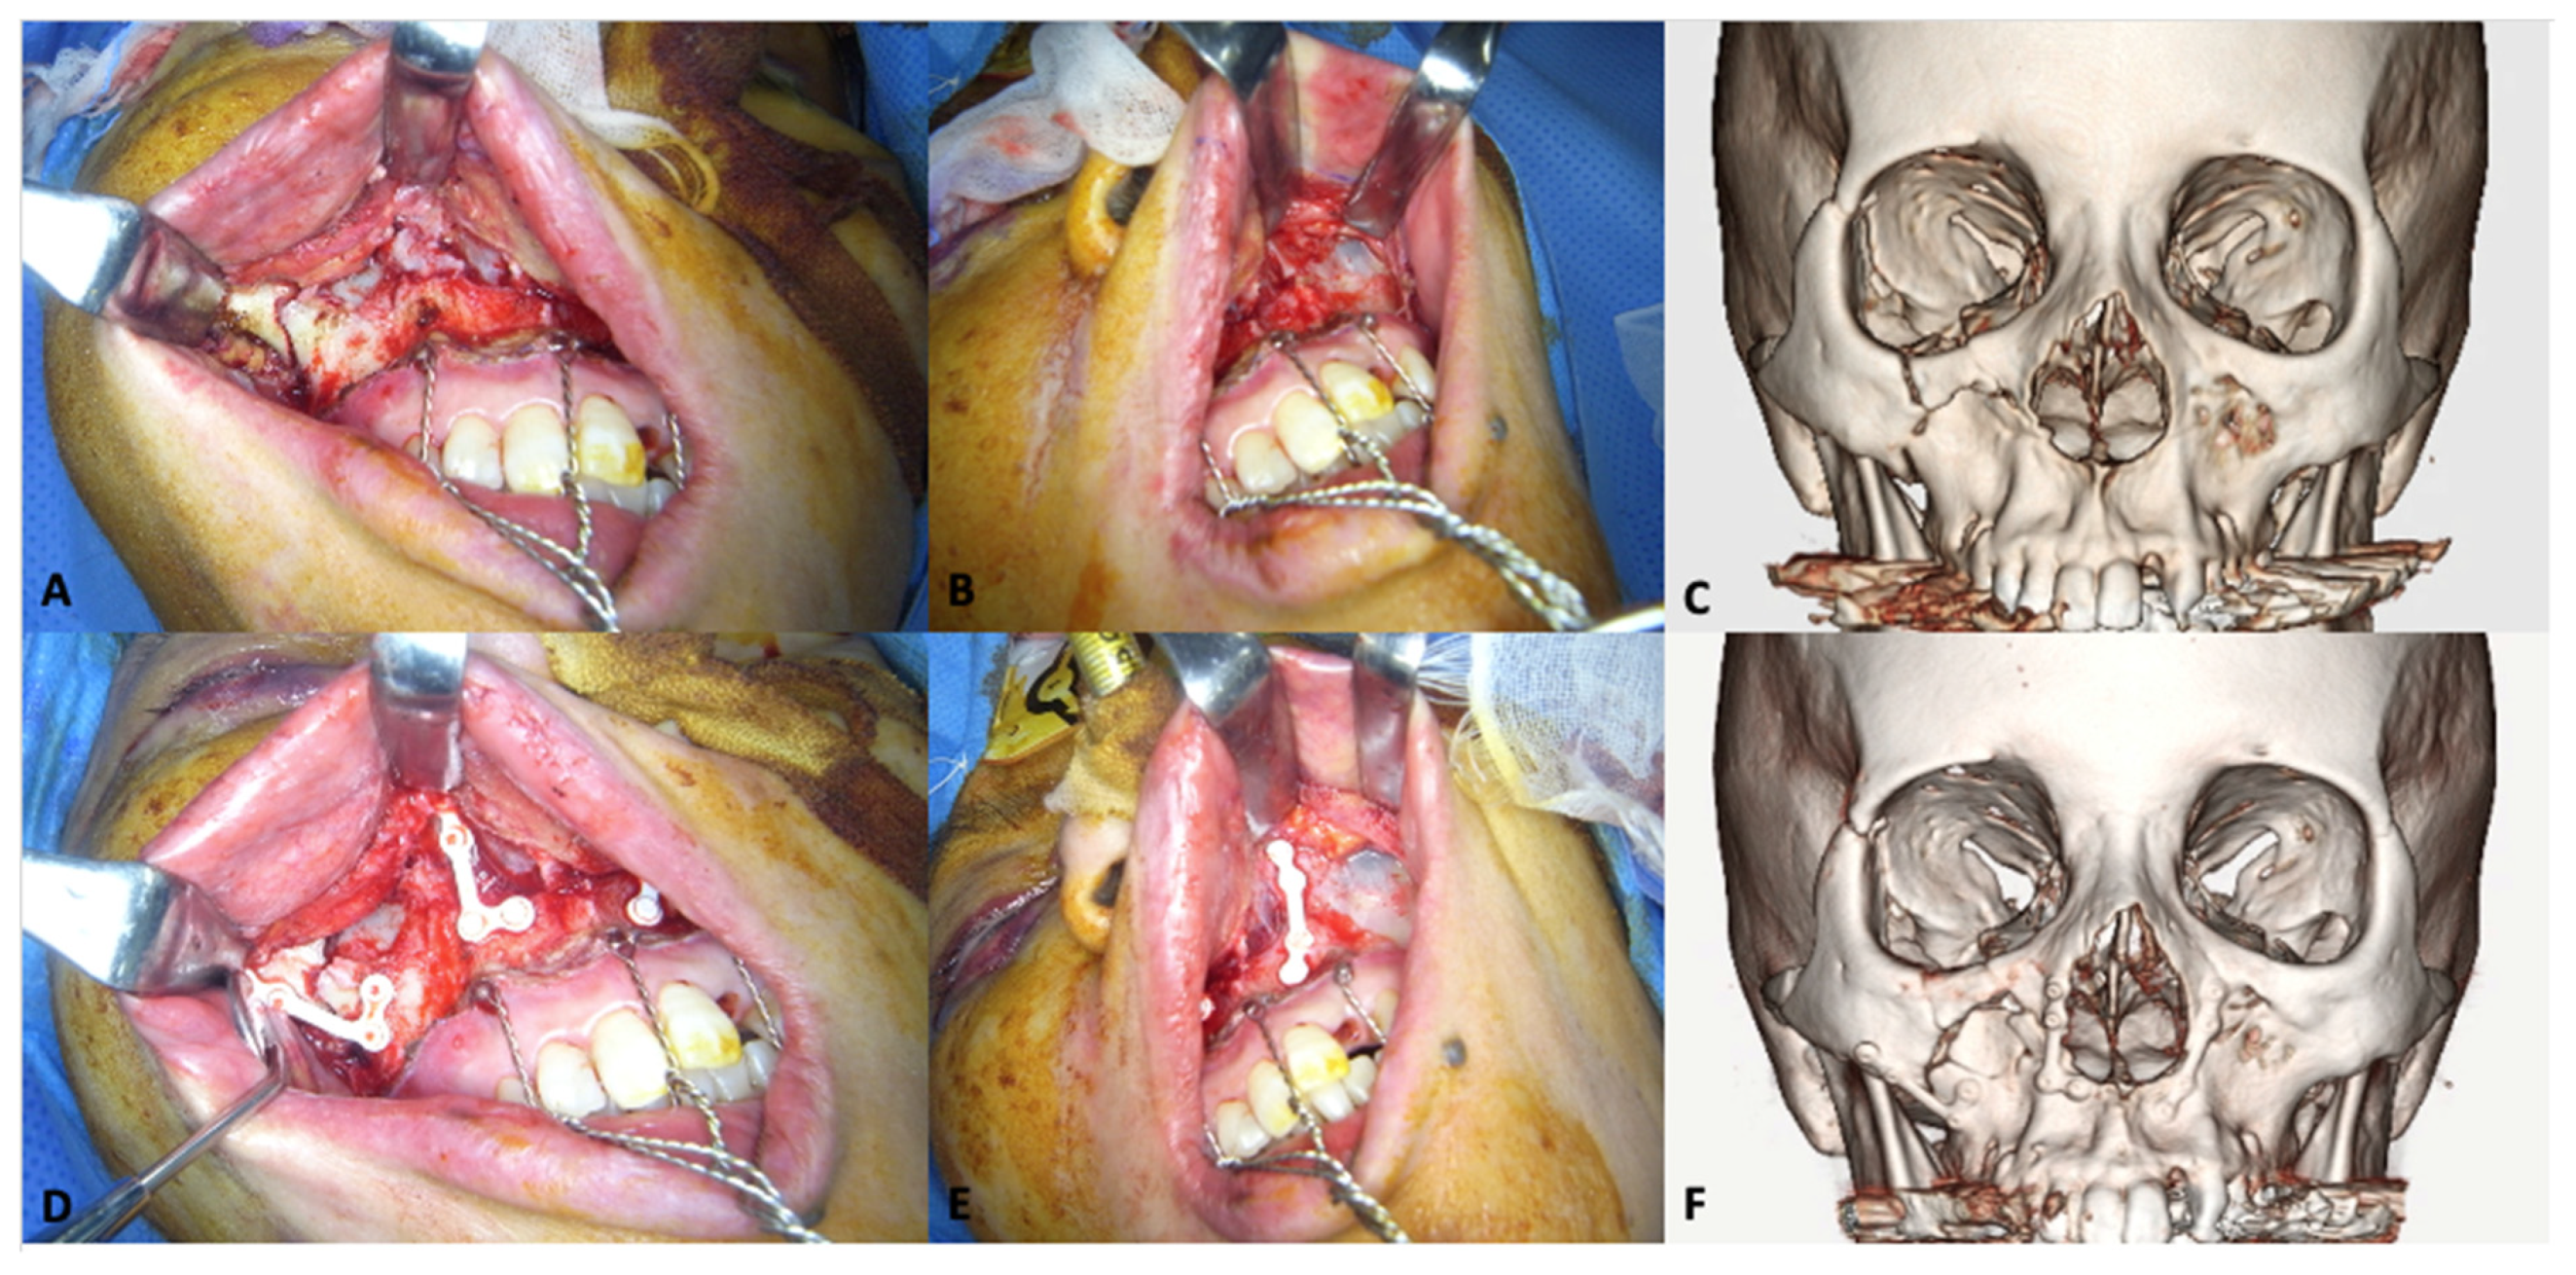

3.1.2. Midfacial Fractures

- Landes, C.; Ballon, A.; Ghanaati, S.; Tran, A.; Sader, R. Treatment of malar and midfacial fractures with osteoconductive forged unsintered hydroxyapatite and poly-L-lactide composite internal fixation devices. J. Oral Maxillofac. Surg. 2014, 72, 1328–1338. [Google Scholar] [CrossRef] [PubMed]

- Sukegawa, S.; Kanno, T.; Katase, N.; Shibata, A.; Takahashi, Y.; Furuki, Y. Clinical Evaluation of an Unsintered Hydroxyapatite/Poly-L-Lactide Osteoconductive Composite Device for the Internal Fixation of Maxillofacial Fractures. J. Craniofac. Surg. 2016, 27, 1391–1397. [Google Scholar] [CrossRef] [PubMed] [Green Version]

- Hayashi, M.; Muramatsu, H.; Sato, M.; Tomizuka, Y.; Inoue, M.; Yoshimoto, S. Surgical treatment of facial fracture by using unsintered hydroxyapatite particles/poly l-lactide composite device (OSTEOTRANS MX(®)): A clinical study on 17 cases. J. Cranio-Maxillofacial Surg. 2013, 41, 783–788. [Google Scholar] [CrossRef] [PubMed]